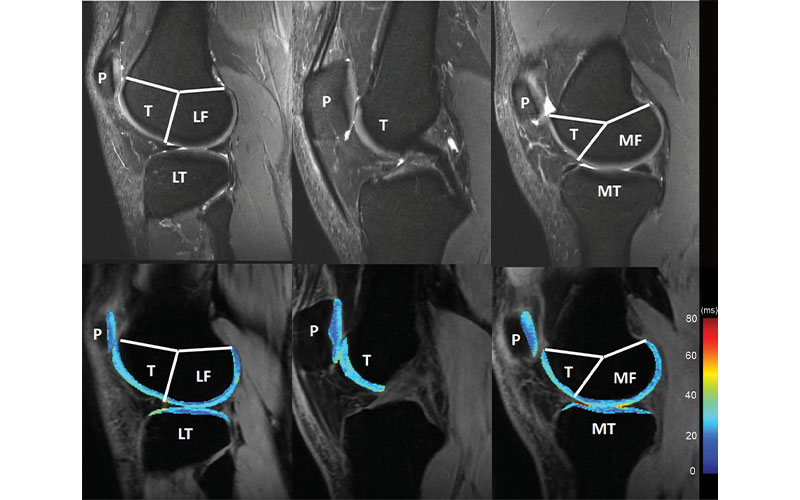

Knee cartilage compartments with anatomic labels implemented in lateral (left side), central (middle), and medial (right side) MRI obtained with an intermediate weighted fat-saturated fast-spin-echo sequence (top row) and a spin-lattice relaxation time constant in rotating frame (T1r) magnetization-prepared angle-modulated partitioned k-space spoiled gradient echo snapshots sequence (bottom row, T1r maps). Study was performed without administration of intravenous gadolinium-based contrast material. The lateral femur (LF)/medial femur (MF) and lateral tibia (LT)/medial tibia (MT) can be further divided into subcompartments on the basis of meniscus anatomy according to Eckstein et al. P = patella, T = trochlea. Chalian et al, Radiology 2021 301; 7 ©RSNA 2021